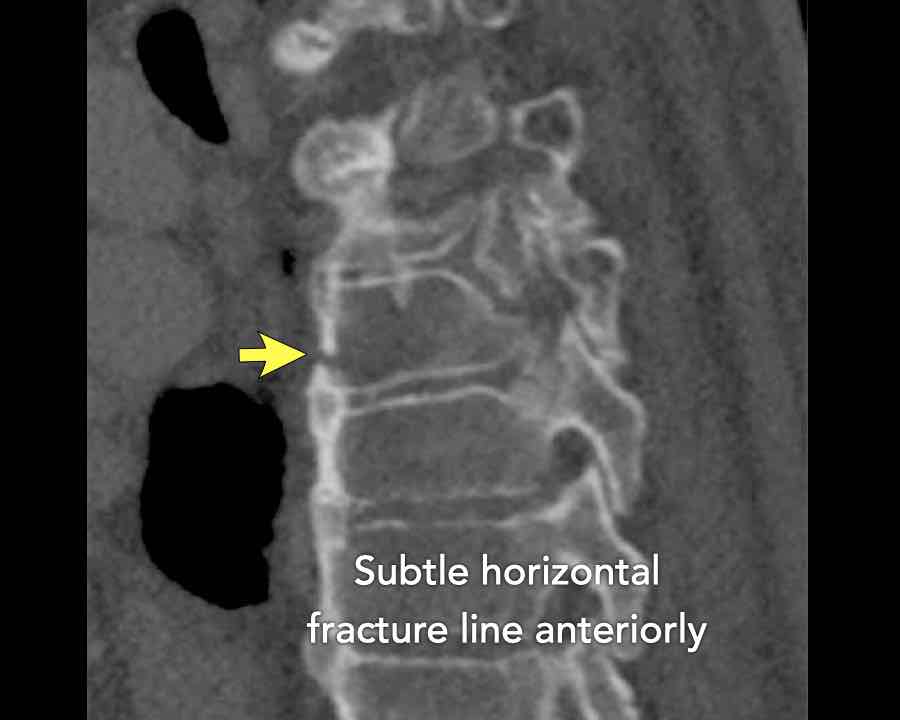

Scroll through images.

What are the findings?

Findings

- C injury? No.

- Signs of a rigid spine?

Yes (DISH), so a B3 injury is very likely. - A subtle fracture on the anterior vertebral body (arrows).

- No separation, probably due to positioning of patient in the scanner

Conclusion

Injury type B3.

Yes, a B3 injury is very likely. - A subtle fracture on the anterior vertebral body.